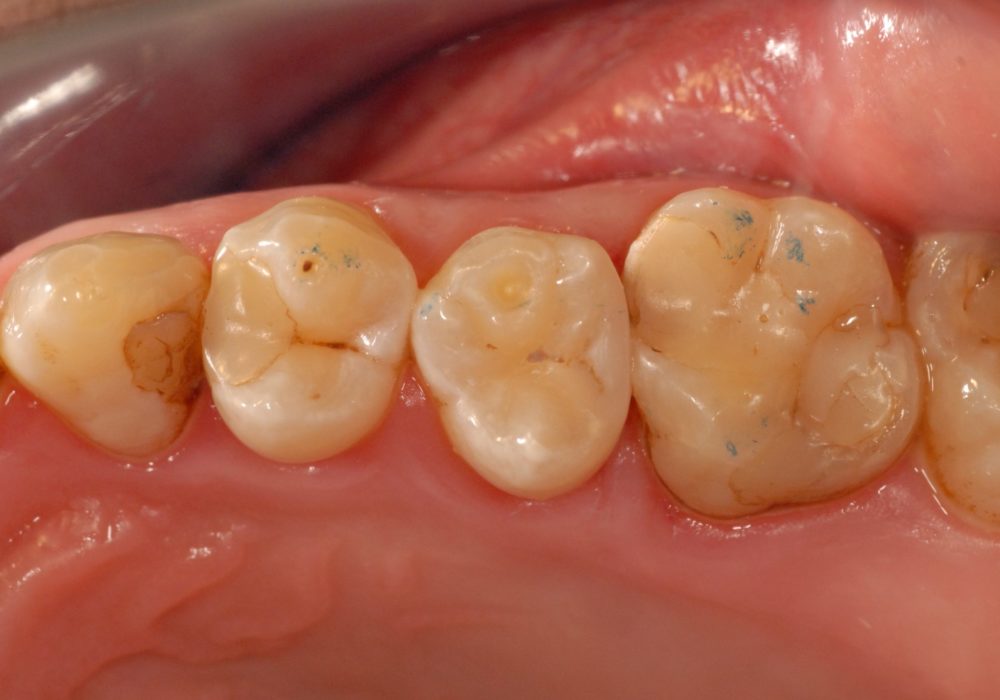

Pacjent zgłosił się z powodu głębokiego ubytku w górnym zębie przedtrzonowym powodującym okresowe dolegliwości bólowe przy jedzeniu

Całkowicie opracowano ubytek, wykonano wytrzymałe i estetyczne wypełnienie kompozytowe będące praktycznie nie do odróżnienia w tkankami własnymi zęba